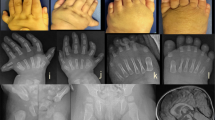

A 20-week fetus with severe skeletal dysplasia was terminated. The 38-year-old multigravida female who carried the affected fetus had a history of two abortions and two first-trimester miscarriages (Fig. 1a). Her second fetus had shortened limbs and a giant bladder (Fig. 1a, II-2). During this pregnancy, antenatal ultrasound examination revealed ventriculomegaly, shortening of long bones, abnormal digits, cleft palate, low-set ears, omphalocele, imperforate anus, and bilateral hydronephrosis at 16 weeks, leading to a strong suspicion of lethal skeletal dysplasia.

a Schematic representation of the missense FLNA variants in males in the region encoding the concerned protein domains. The red arrowhead indicates the case, and the black arrowhead indicates the lethal outcomes. b Clinical characterization and pathogenesis of the FLNA variants identified in nonsurviving males.